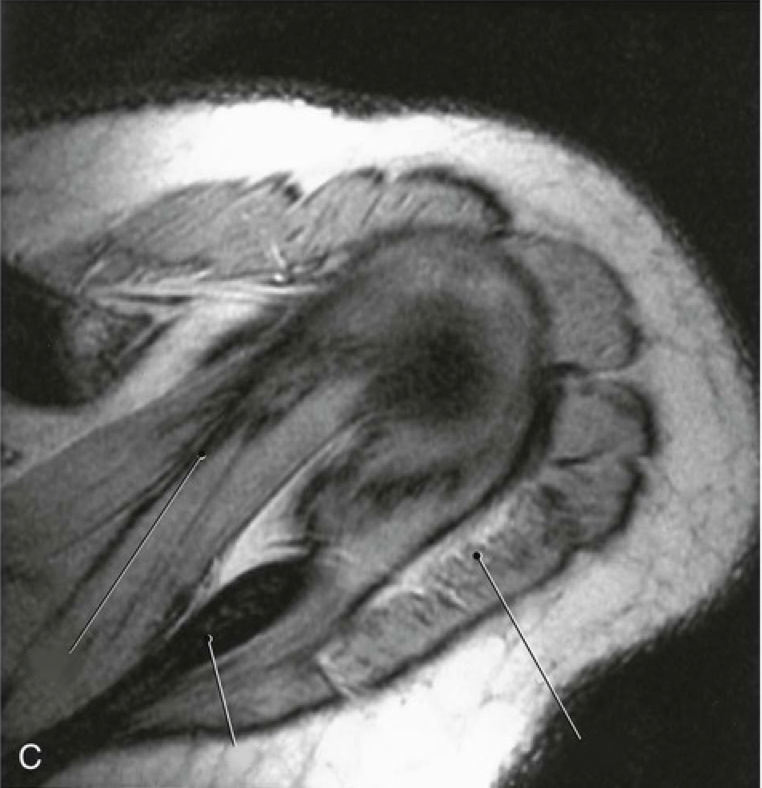

24474d13-c631-43f0-b8a7-2368ffaeab8c (image/jpeg)

Answer

supraspinatus muscle

scapular spine

deltoid muscle